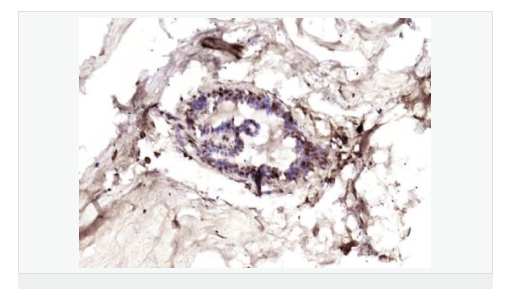

產(chǎn)品應(yīng)用ELISA=1:5000-10000 IHC-P=1:100-500 IHC-F=1:100-500 IF=1:100-500 (石蠟切片需做抗原修復(fù))

細(xì)胞定位細(xì)胞核 細(xì)胞漿 細(xì)胞膜